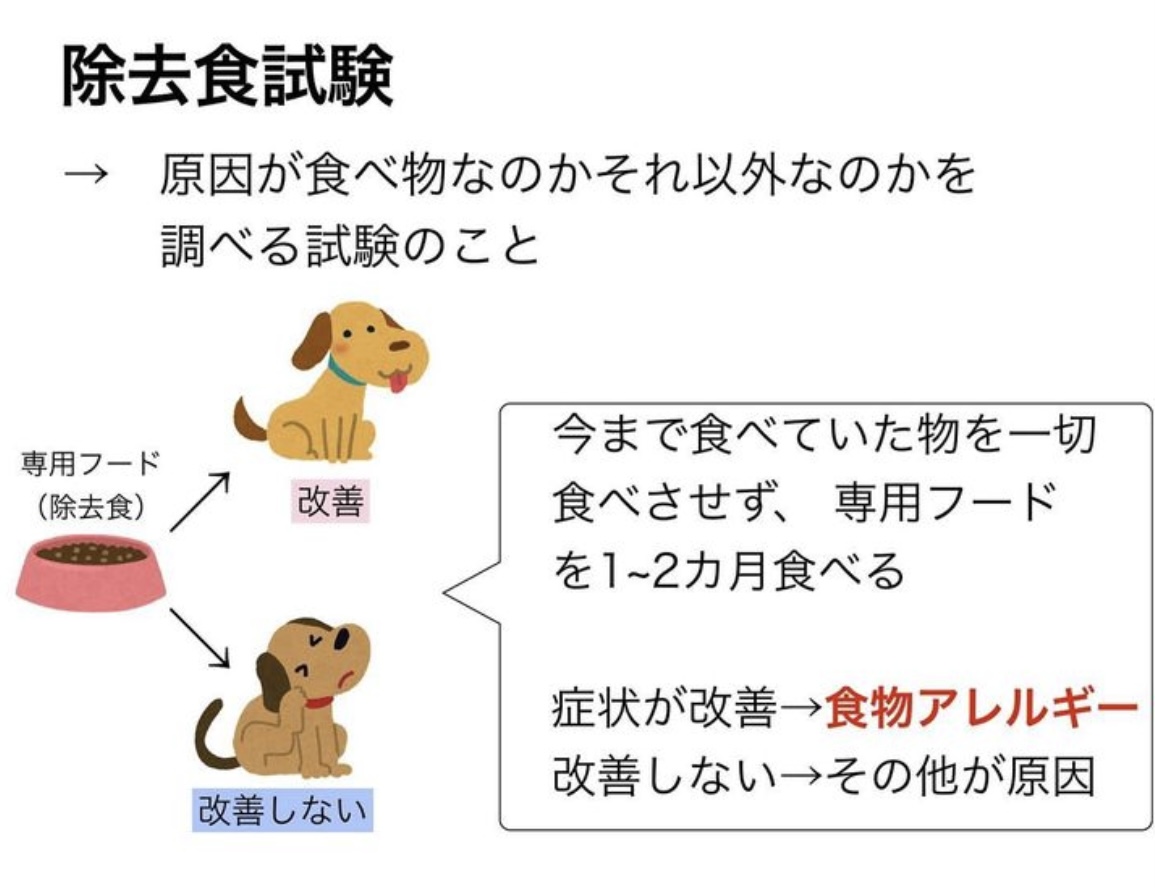

皮膚の仕組み ・正常な皮膚 表面の角質の層が規則正しく並んでいるので、細菌やマラセチア、アレルゲンの侵入を防ぎます。 ・アレルギー性皮膚炎 皮膚の表面の角質バリアが剥がれ、角質同士の間…